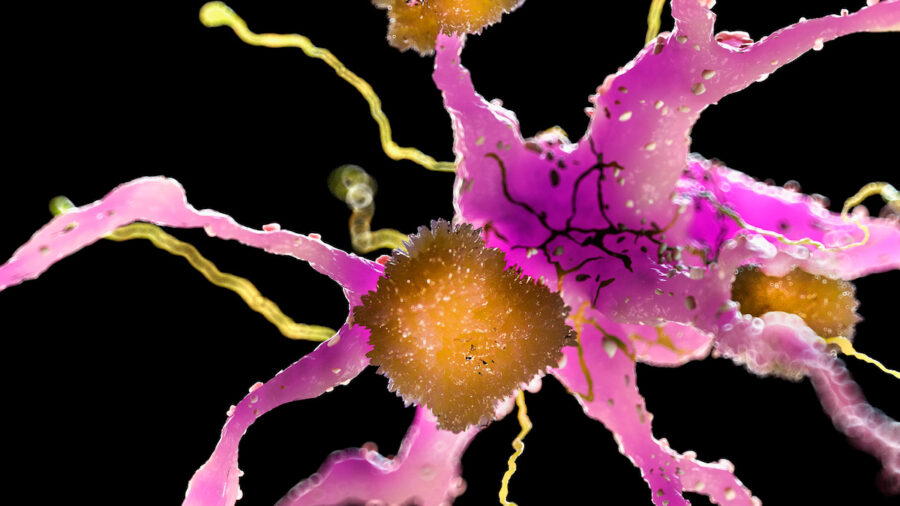

رویکرد جدید آنها در درمان آلزایمر، (سد خونی-مغزی) را نه صرفاً مانعی برای عبور، بلکه دروازهای میداند که نیاز به ترمیم دارد. سد خونی-مغزی، دستگاه گردش خون مغز را از بقیه بدن جدا میکند و با جلوگیری از ورود سموم و عوامل بیماریزا، از مرکز آگاهی انسان محافظت مینماید؛ اما همین سد، مانع ورود بسیاری از داروها نیز میشود.

رویکرد نوآورانه این پژوهش از فرضیهای نوظهور پشتیبانی میکند که بر اساس آن، سد خونی-مغزی در بیماران آلزایمری تضعیف یا دچار اختلال میشود و همین امر موجب تجمع مواد زائد در مغز میگردد.

به گفته تیم بینالمللی پژوهشگران، در بیماری آلزایمر، مشکل تنها محدود به دسترسی نیست؛ بلکه خود سامانهی انتقال در مغز نیز بهطور بیماریزا دچار اختلال عملکرد شده است. دانشمندان در این مطالعه از نانوذرات نه بهعنوان حاملهای غیرفعال دارو، بلکه بهعنوان عوامل فعال تغییر استفاده کردند و از این طریق توانستند جریان عبور مواد از سد خونی-مغزی را اصلاح کرده و فرآیند پاکسازی پلاکهای آمیلوئیدی را در مغز موشها بازگردانند.

به گفته پژوهشگران، نانوذرات مانند مهندسان ریزمقیاس رفتار سلولی عمل میکنند و فرآیند ترمیم را در سطح مولکولی هدایت مینمایند. هدف نهایی آنها پروتئینی به نام LRP1 اندوتلیال است که در حذف پلاکهای آمیلوئید بتا در ناحیه سد خونی-مغزی نقش دارد.